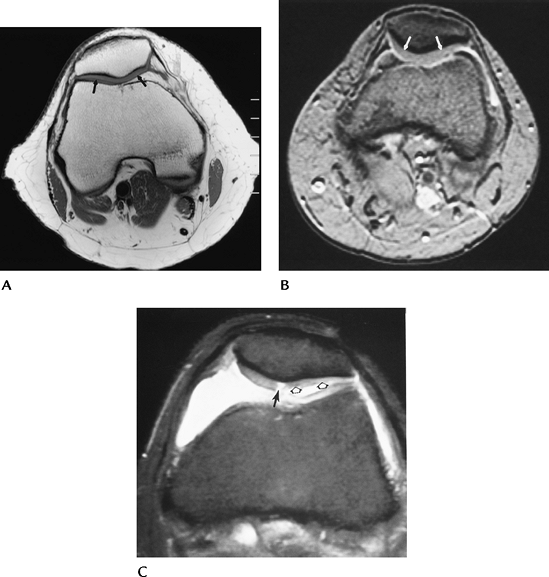

FIGURE 5-53 Sagittal (A) and axial (B)

T2-weighted MR images after patellar dislocation with fluid–fluid levels, retinacular tear, and shaving of the patellar articular cartilage (arrow). |